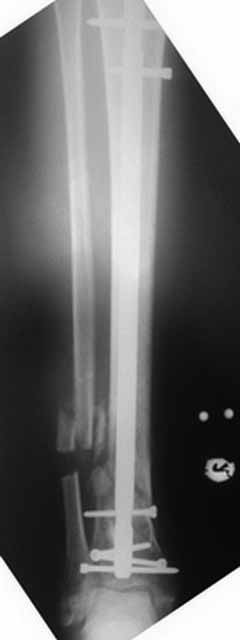

Это гипотрофический ложный сустав. Проблем видится несколько:

1. нарушение трофики в месте перелома.

2. после фиксации в аппарате Илизарова на рентгеногнрамме имеются признаки спицевого остеомиелила. В настоящи момент хотя свищей нет с мая 2011 нет опасно ли фиксировать голень стержнем?

Да уж! Ни один из 3-х оперативных методов предшествующего лечения не был исполнен правильно. Везде был серьезный брак. Хотя любой из методов вполне мог бы и должен был бы привести к сращению,...если бы, да кабы.. В результате имеем то, что имеем. Что делать? Во-первых - подумать. Во-вторых - еще раз подумать. В третьих - еще больше подумать.

Иван, Вам видится зона перелома мертвой, а мне вовсе нет. Есть ли возможность сделать сцинтиграфию с технецием? Это может доказать нежизнеспособность или воспаление концов. Тогда есть резон для такой "крайней" меры как резекция. Есть ли клинические признаки инфекции в области первичной раны?, п\операционных рубцов?, в местах проведения спиц (нет ли спицевого остеомиелита)?.. В общем, вопросов может быть много.

На основании каких признаков Вы решили, что кость мертвая! Имеется гиперпластический ложный сустав, как результат недостаточно стабильной фиксации ан предыдущих этапах лечения. В данном случае необходимо решение следующих вопросов:

Примерная ситуация. Пациент 37 лет. Синтезировали где-то пластинкой. Попал к нам через 2 месяца.

19 апреля убрали через проколы пластину с винтами, пересекли fibula, наложили аппарат.

Немного потянули по оси, убрали вальгус, ротацию. 22 апреля (на 3-е сутки) заштифтовали окончательно. 29 апреля выписали из отделения. На все ушло 10 дней.